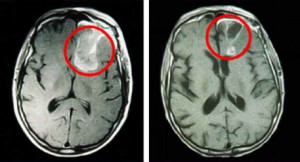

Поэтому на лечение направляются больные с неутонченным диагнозом. Он ставится на основании жалоб, оценки результатов функциональных исследований и проб, данных рентгенологического исследования, компьютерной томографии или МРТ. Окончательное подтверждение (или исключение) диагноза рака мозга проводится в онкологическом стационаре.